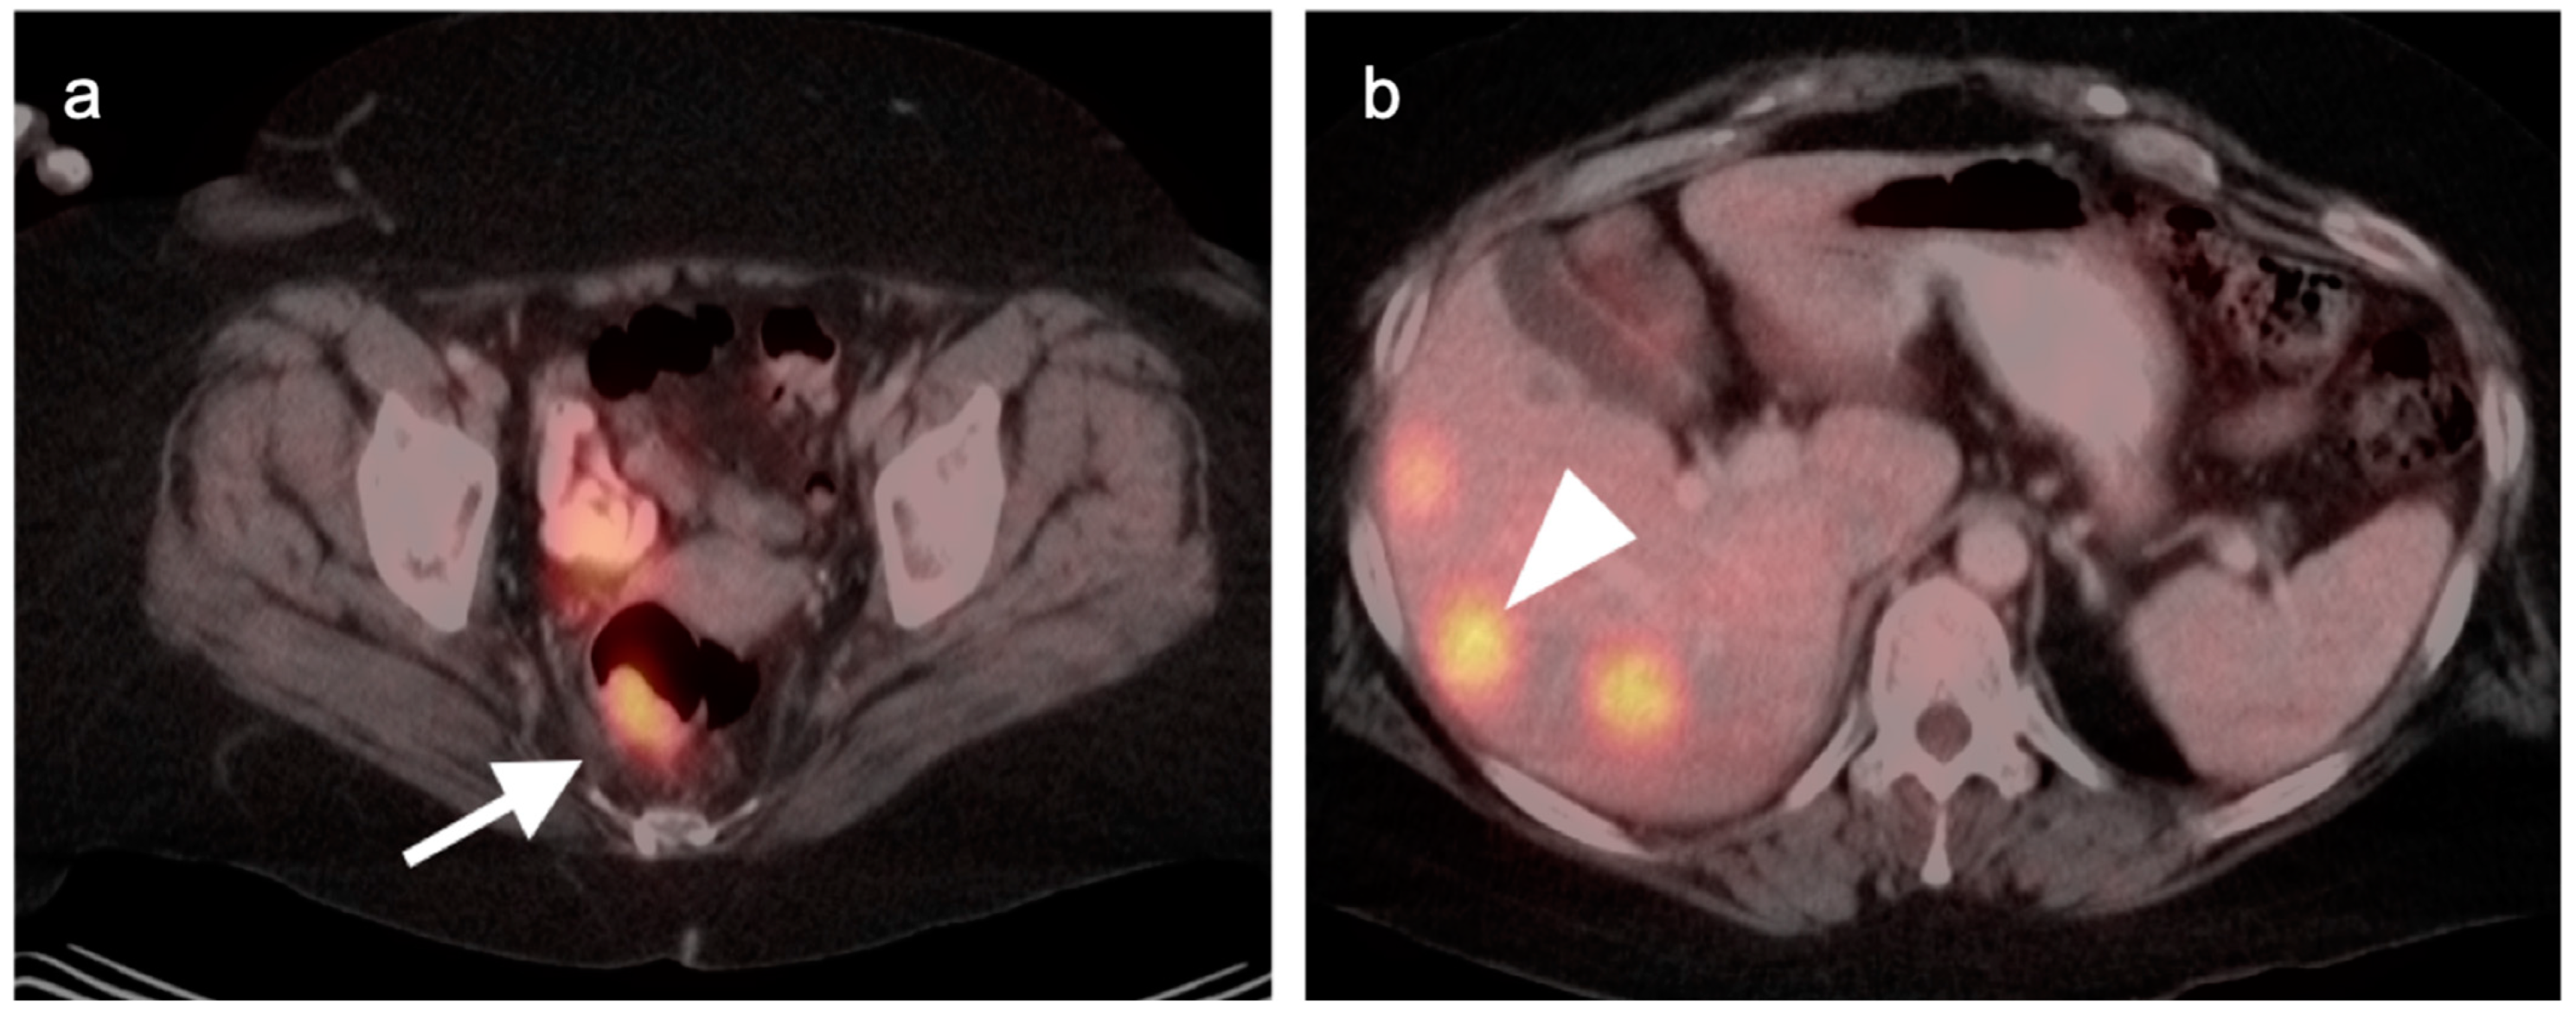

10. Anal Carcinoma